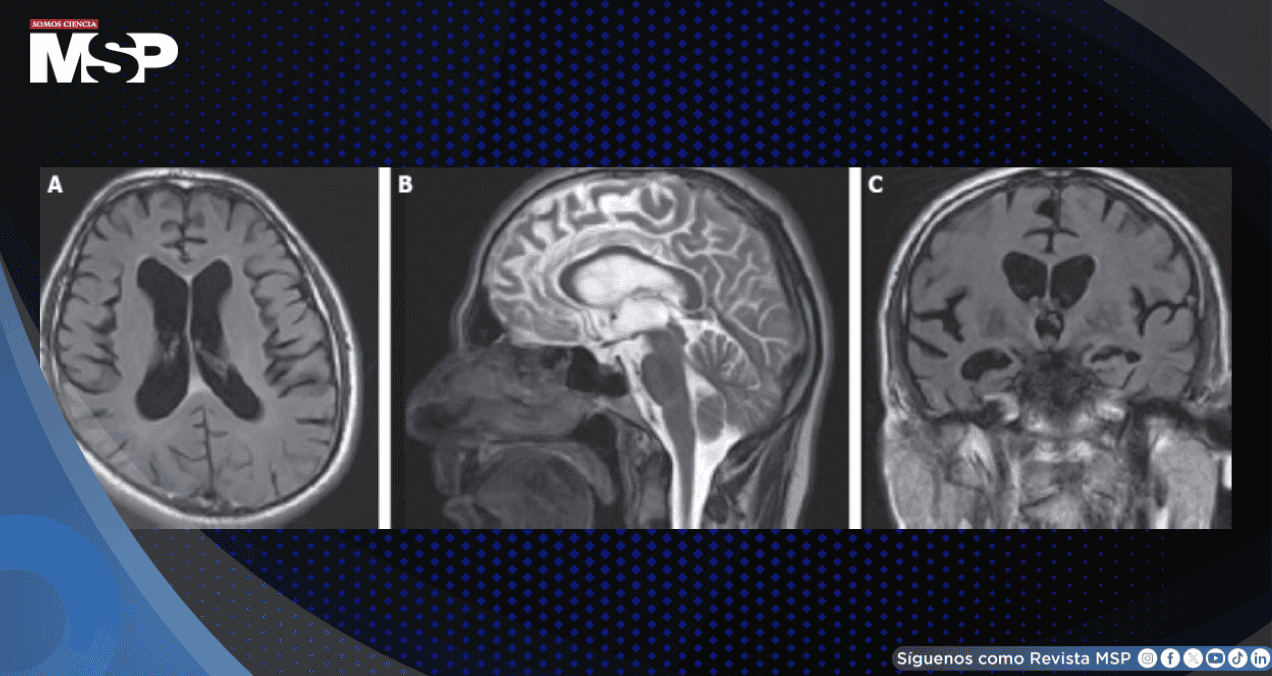

Las imágenes de resonancia magnética craneal revelaron atrofia cerebral y cerebelosa global, así como secuelas de traumatismo en la sustancia blanca subcortical del lóbulo parietal derecho, sin evidencia de realce con contraste. Ante estos hallazgos, se decidió realizar una punción lumbar para analizar el líquido cefalorraquídeo.